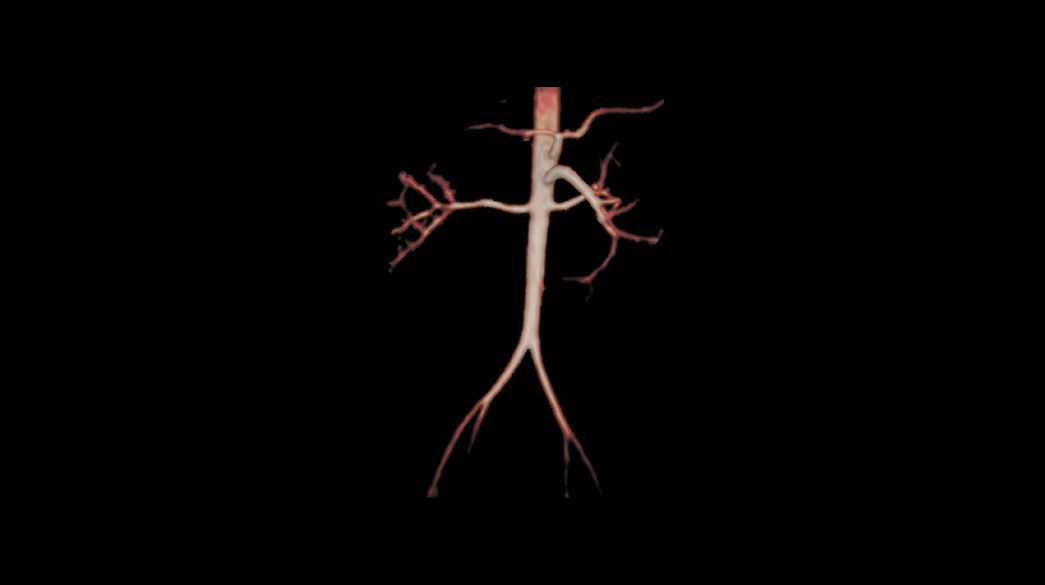

Inhance-Suite1040-x-585

ViosWorks1040-x-585

TRICKS1040-x-585

Read case study